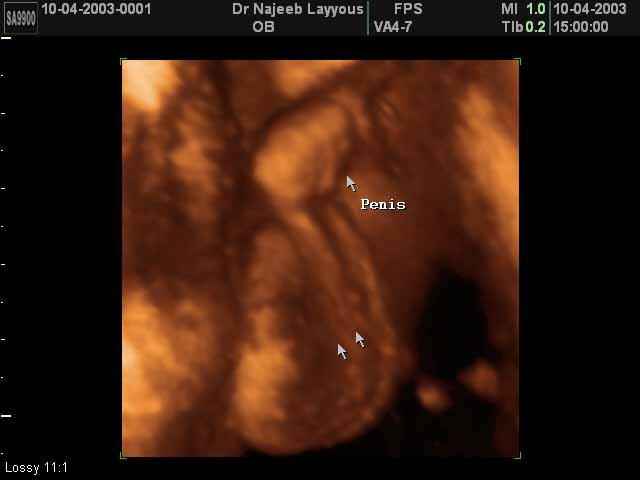

- 3D Photos échographie des parties du fœtus